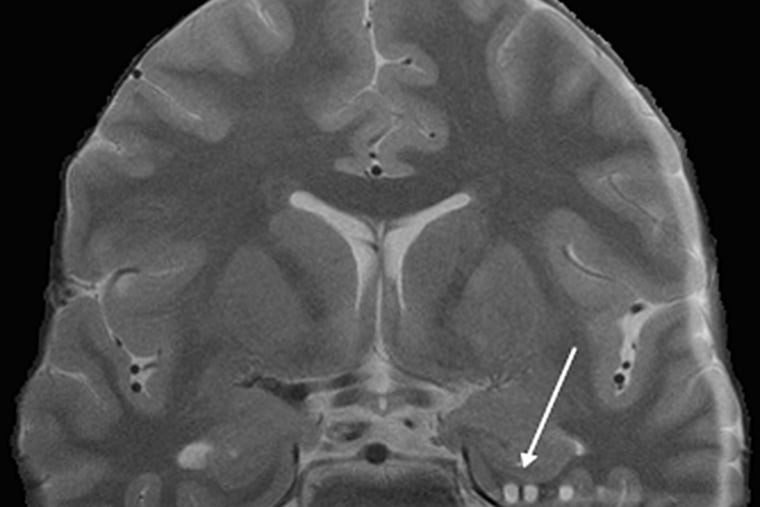

Abbildung der Aktivitäten eines stimulierten Gehirns: Schon heute gelingt es Wissenschaftlern, ansatzweise zu erkennen, über welche Worte, Bilder, Töne und Entscheidungen Versuchspersonen nachdenken.

Mentale Holzschnitte: Dylan Haynes, der Leiter des Berlin Center for Advanced Neuroimaging entschlüsselt im Kernspin-Tomografen Ja-Nein-Entscheidungen. 400 Milliarden Dollar Marktpotential kann Gehirn-Computer-Interaktion in zehn Jahren erreichen.

Doch um wirklich zu verstehen, was die Menschen bewegt, reicht es den Forschern nicht, nur Hirnströme von außen abzugreifen. Sie müssen direkt verfolgen, welche Spuren das Denken im menschlichen Gehirn hinterlässt. Solche Einblicke ermöglichen Kernspin-Tomografen. Diese röhrenförmigen Geräte sind so groß wie Kleintransporter. Sie können Aufnahmen aus dem Körperinneren erzeugen, ähnlich schichtweisen Röntgenbildern. Zwei davon stehen in einem Backsteingebäude auf dem Gelände der Berliner Uniklinik Charité. Vor der runden Öffnung jedes Tomografen steht eine Liege, auf der Probanden in die Röhre geschoben werden. Sie erzeugt ein starkes Magnetfeld, das zwar für den Menschen ungefährlich ist, es aber dennoch erlaubt, genaue Bilder von der Struktur und der Aktivität des Denkapparates zu erzeugen. Bilder, auf denen das Gehirn aussieht wie eine flache walnussartige Scheibe mit bunten Flecken.

Die zeigen, welche Hirnareale gerade viel oder wenig Sauerstoff verbrauchen. Da bei denselben Gedanken ähnliche Muster entstehen, können Forscher im Lauf der Versuche immer besser erkennen, woran der Proband gerade denkt.

Sie sehen sogar, welche Entscheidung er treffen wird. Das hat John-Dylan Haynes in mehreren Experimenten gezeigt. Der renommierte Hirnforscher leitet das Berlin Center for Advanced Neuroimaging, in dem die Scanner stehen. In einem Experiment bat der Professor seine Probanden, sich eine Sportart vorzustellen. Ihre Hirnaktivität signalisierte, wofür sie sich entschieden hatten, noch bevor ihnen selbst der Entschluss bewusst wurde.